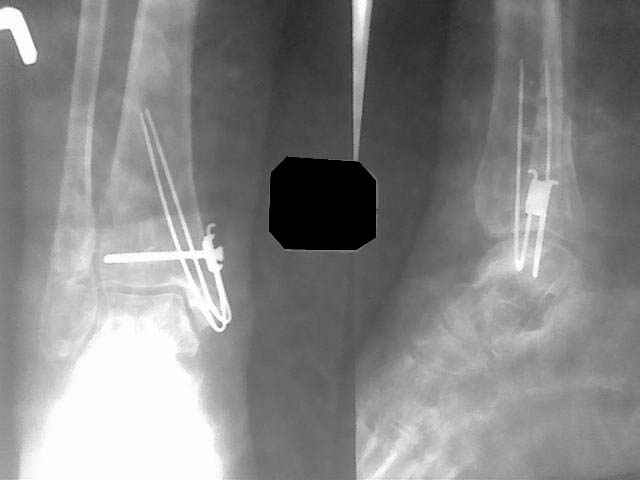

В данном случае - ложный сустав внутренней лодыжки на фоне оперативного лечения кортикальным винтом 3,5 и спицей. Часть внутренной лодыжки была лизирована. Проведена костная аутопластика. Результат налицо.

Ув. коллега. Хотелось бы посмотреть рентгенснимки до операции. Был ли поврежден синдесмоз. На Ваших рентгенограммах нет признаков остеоартроза. Вполне вероятно, что Вы получили хорошие функциональные

результаты. У моей пациентки случай неординарный. Оперировать надо один раз, если неудачно - она больше ко мне не прийдет. В районе нельзя ошибаться, авторитет быстро упадет. Благодарю за искреннее желание помочь.

Ув. коллега. Снимки постараюсь найти, они у пациентки. Вкратце: травма 7 месяцев назад. 2х лодыжечнай перелом со смещением отломков, с подвывихом стопы. Мое мнение что синдесмоз был поврежден, хотя мнения разошлись, но позиционный винт был поставлен. Рецидивирующие свищи п/о рубцов. Металл был удален через 2 месяца. Далее больная попала ко мне с ложным суставом вн. лодыжки. Далее вы видели.